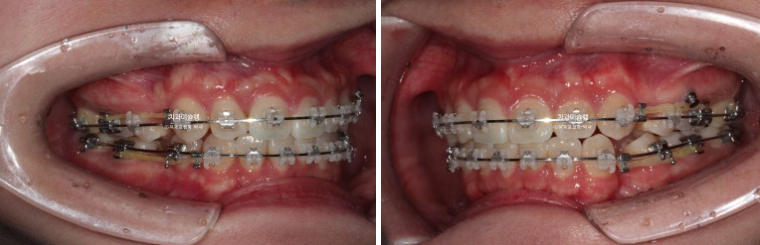

중심선은 잘 맞고 과개교합도 해소가 되었습니다.

어금니 교합은 물샐틈 없는 1급 교합관계 입니다.